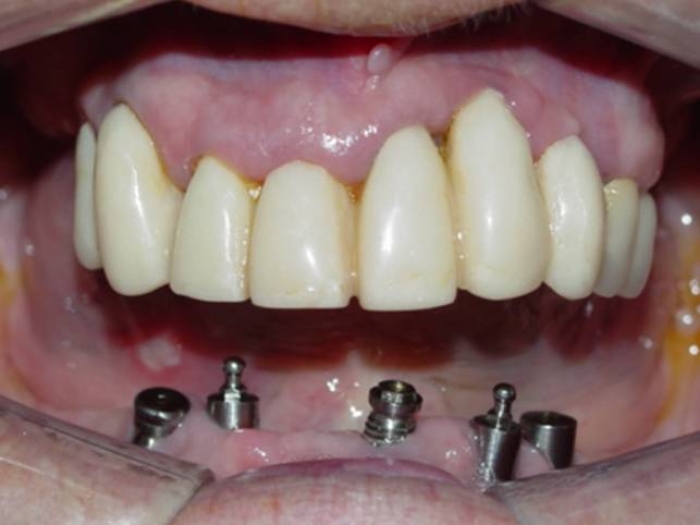

Raio X com implantes Cone Morse e próteses fixas em porcelana

Próteses fixas em porcelana sobre implantes